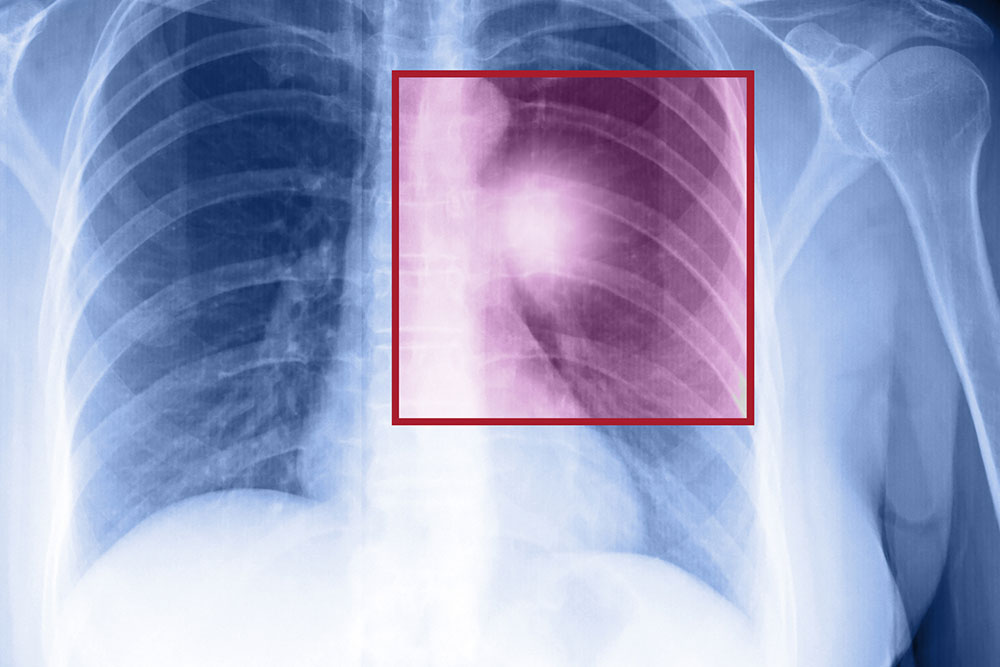

- Chest X-ray which provides detailed images of the lungs.